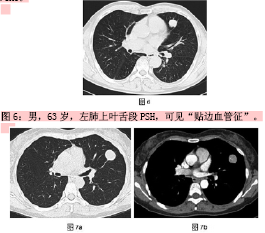

回顾经典--硬化性肺血管瘤